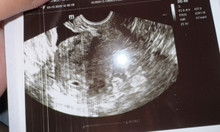

5weeks & 6days base on LMP pero wala pa makita kahit anong nakita kahit Sac

May same din ba dito na walang nakita kahit sac? Pero nagtuloy ang pregnancy? baka daw late since pcos daw ako 🥲 pero dapat 5weeks na ako at ineexpect ko na may laman na at heartbeat pero kahit sac pala wala makikita. Suspect for ectopic daw pero wala din nakita both fallopian tube ko 🥹 kinakabahan nanaman ako. Nextweek follow up ultz#AskingAsAMom #Needadvice